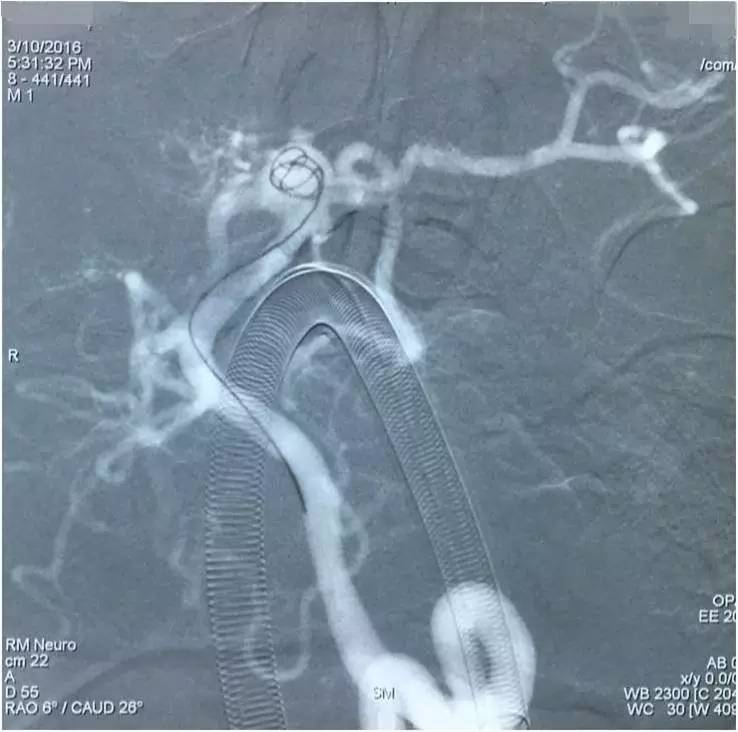

▼Headway17完成支架释放后,经支架网眼导入左小脑上动脉瘤内。这里要说明的是,LVIS JR的网眼是比较容易穿过的。

▼经Headway17送入弹簧圈栓塞左侧小脑上动脉瘤。

▼Headway17完成左小脑上动脉瘤的栓塞后,再经支架网眼导入右PCA,将第二枚LVIS JR 3.5*23支架跨瘤颈释放入右PCA-基底动脉,如此完成了Y型支架的释放,为基底动脉顶端动脉瘤的栓塞工程摆好了脚手架。

▼微导丝经支架内部弓背进入右PCA,Headway17微导管跟进,目的是加强第二枚支架(穿过了第一枚支架的网眼)的扩张性和贴壁性。